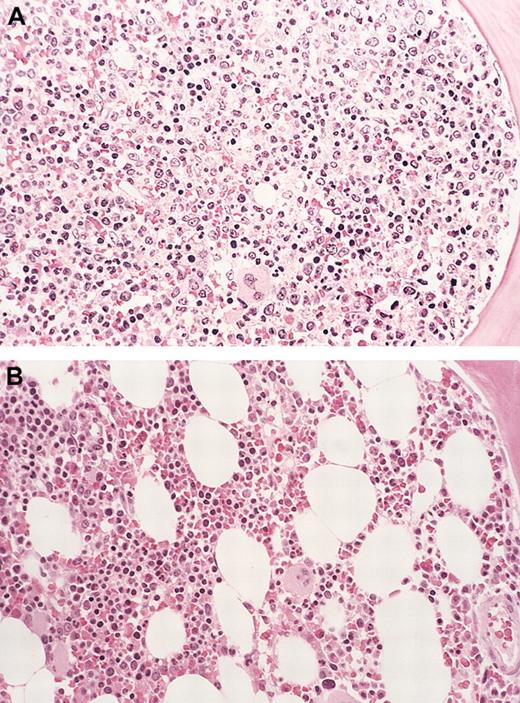

Eosinophil infiltrate and degranulation.

(A) Eosinophilic myocarditis (case 1). Low-power photomicrograph showing the presence of a patchy interstitial infiltrate of eosinophils. These infiltrates were focally associated with myocyte damage (hematoxylin-eosin). (B) Eosinophil major basic protein (MBP). Step section of microscopic field shown in (A) stained for eosinophil MBP. Note marked MBP deposition, much of it extracellular, indicating eosinophil degranulation (immunofluorescence). Original magnification for both panels, × 100.

The patient had a prompt and dramatic decrease in circulating eosinophils, which were undetectable after 10 days of imatinib therapy. He, however, developed progressive dyspnea and orthopnea in the interim from acute left ventricular dysfunction with cardiogenic shock and required intravenous pressor support. A chest X-ray revealed new bilateral pulmonary infiltrates, and an echocardiogram revealed new-onset severe generalized left ventricular (LV) hypokinesis (LV ejection fraction [LVEF] decreased from 71% to 10% after 8 days of therapy). Following emergent cardiac catheterization, which revealed normal coronary vessels, placement of an intra-aortic balloon pump (IABP) became necessary for hemodynamic support. A right ventricular endomyocardial biopsy was performed at the time of cardiac catheterization. The patient was started on high-dose steroids (1 g methylprednisolone given daily) with rapid improvement of hemodynamic parameters within a few hours of starting steroid therapy, and he was weaned off pressors after 72 hours. A follow-up echocardiogram at this time revealed that the LVEF had improved to 30%. Review of the endomyocardial biopsy specimen confirmed eosinophilic myocarditis with evidence of eosinophil degranulation and focal myocyte damage (Figure1). At the time of dismissal from the hospital (hospital day 7), he was significantly improved, and a follow-up echocardiogram revealed an LVEF of 46%. The peripheral eosinophil count was 290 × 109/L at dismissal. After LV function recovery (LVEF, 55%-60% at 4 weeks after imatinib discontinuation), the patient was rechallenged with imatinib (100 mg/day), with concurrent prednisone (60 mg/day on days 1-3, 20 mg/d on days 4-6, with slow taper thereafter), and close monitoring of cardiac function with serial echocardiograms. A symptomatic left lower extremity deep venous thrombus was noted at this visit for which anticoagulation was started. The patient tolerated imatinib retreatment well, without recurrence of cardiac toxicity. At last follow-up, the patient was asymptomatic, without evidence of peripheral eosinophilia (Table 1).